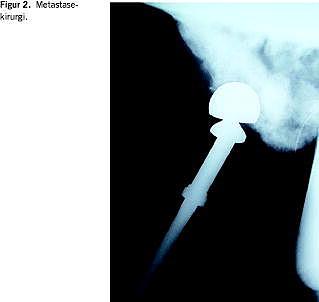

Udviklingen af bedre teknikker inden for ekstremitetsbevarende tumorkirurgi, protesekirurgi, traumekirurgi og degenerative ryglidelser har kunnet overføres til metastasekirurgi [7]. Dette har sammen med tiltagende brug af præoperativ tumorembolisering og bedre anæstesimetoder øget mulighederne for rekonstruktiv kirurgi ved patologiske frakturer og behandling af truende paraplegi og inkontinens fra spinalkompression pga. knoglemetastaser. For at sikre stabiliteten bruges der i stigende omfang proteser ved lednære metastaser og marvsøm i rørknogler (Figur 2 ). Opfyldning af metastasekaviteten med knoglecement kan øge stabiliteten. Skinneosteosyntese må betragtes som obsolet. Inden for rygkirurgien er der tendens til mere radikal tumorfjernelse og stabilisering end tidligere.